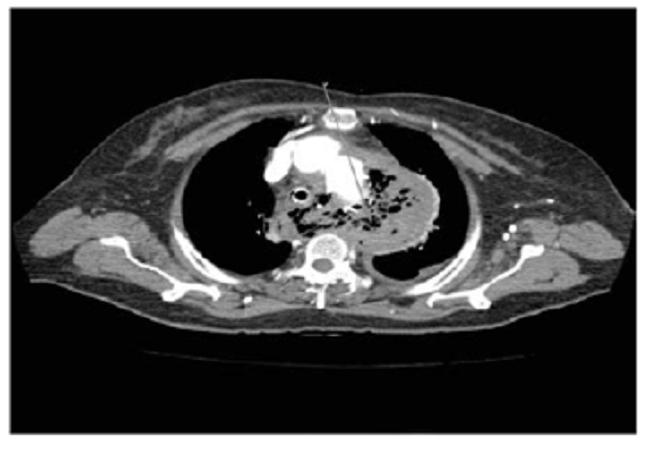

Se decidió practicar una nueva angiotomografía torácica con doble contraste, oral y endovenoso, en la que se observó la endoprótesis en la aorta descendente, extravasación del medio de contaste oral por la pared posterior del esófago, neumomediastino y derrame pleural bilateral, lo que confirmaba una perforación esofágica (figura 3).

Quince días después, la paciente consultó nuevamente al servicio de urgencias por presentar hemoptisis, disnea y deposiciones melénicas. Ingresó taquicárdica e hipotensa con baja perfusión distal. Se diagnosticó choque hipovolémico y se inició reanimación hídrica con hemoderivados; además, requirió asistencia respiratoria y hemodinámica. En la endoscopia de vías digestivas se observó un gran coágulo en el esófago que, al retirarse, dejó ver un defecto en la pared esofágica a 25 cm de la arcada dental, sugiriendo la presencia de una fístula. Se practicó una angiotomografía de tórax en la que se encontró la endoprótesis en buena posición, aunque había signos de mediastinitis y de neumomediastino masivo (figura 8).